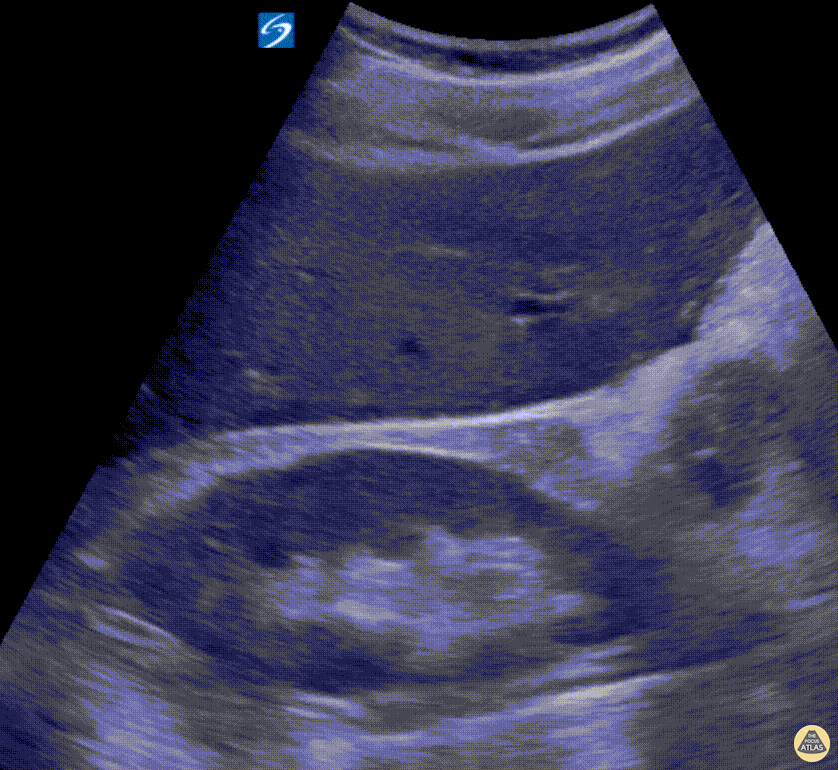

Seen here is a subtle positive RUQ FAST scan in a trauma patient — a pertinent reminder to never stop simply after evaluating Morison's Pouch. Always also trace anteriorly to the lowest part of the liver. Hjalti Már Björnsson @hjaltimb